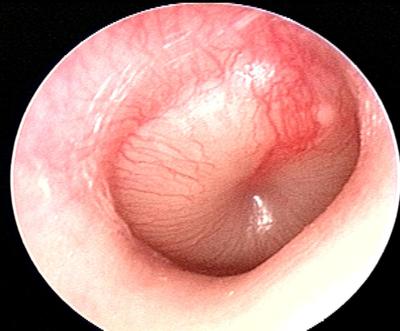

Question 3

Question

Describe the disease shown in this picture!

Answer

Direct contact between keratinizing squamous epithelium in external meatus and mucoperiosteum of middle ear damaged by inflammation

Tx: Remove matrix, perimatrix, eroded bone

Can progress to labryinthitis, meningitis , brain abscess

Fetid otorrhea, purulent

No perforation is observed